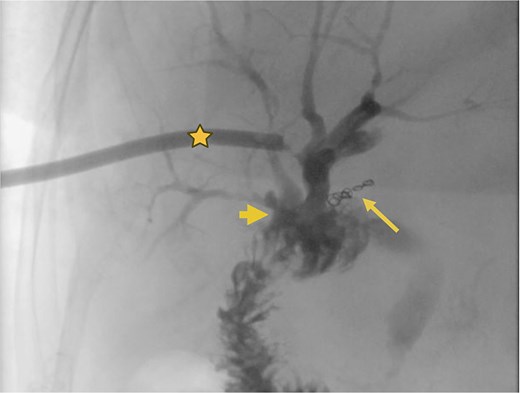

Angiography. (a) Saccular image consistent with a hepatic artery pseudoaneurysm (Segment V). (b) Pre-embolization image of the right hepatic artery showing contrast medium leakage (arrow) from a branch (Segment V) of the right hepatic artery. Right percutaneous catheter (star).

Surgical reconstruction revealed an excluded PRHD and ARHD–LHD continuity with obstruction 10 mm from the confluence. The PRHD catheter was found outside the biliary tract, so a transhepatic Nelaton catheter was placed from inside to out. A neoconfluence of PRHD with ARHD and LHD was created with a 30 mm hepaticojejunostomy. A transanastomotic Nelaton catheter and a supranastomotic ARHD catheter were left in place. Estimated blood loss: 300 cc. In the immediate postoperative period, the patient developed melena and bleeding from the Penrose drain. Cholangiography via the right percutaneous catheter showed no contrast leakage. Angio-CT revealed an 8 × 5 mm saccular lesion in the anterior right hepatic artery (Segment V), consistent with a pseudoaneurysm (Figs 1 and 2). Selective embolization with three microcoils (2 × 3 × 2.3 mm) was successfully performed (Fig. 3). The patient had a favorable recovery, with no further bleeding, and was discharged in stable condition for outpatient follow-up. Control imaging of the ARHD catheter confirmed adequate visualization of all hepatic ducts, allowing catheter removal (Fig. 4).